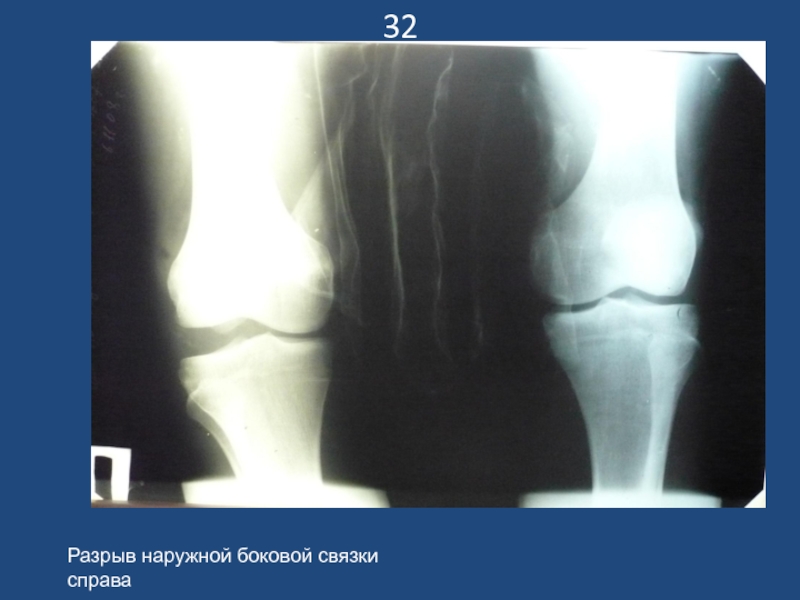

Слайд 3332

Разрыв наружной боковой связки справа

32Разрыв наружной боковой связки справа